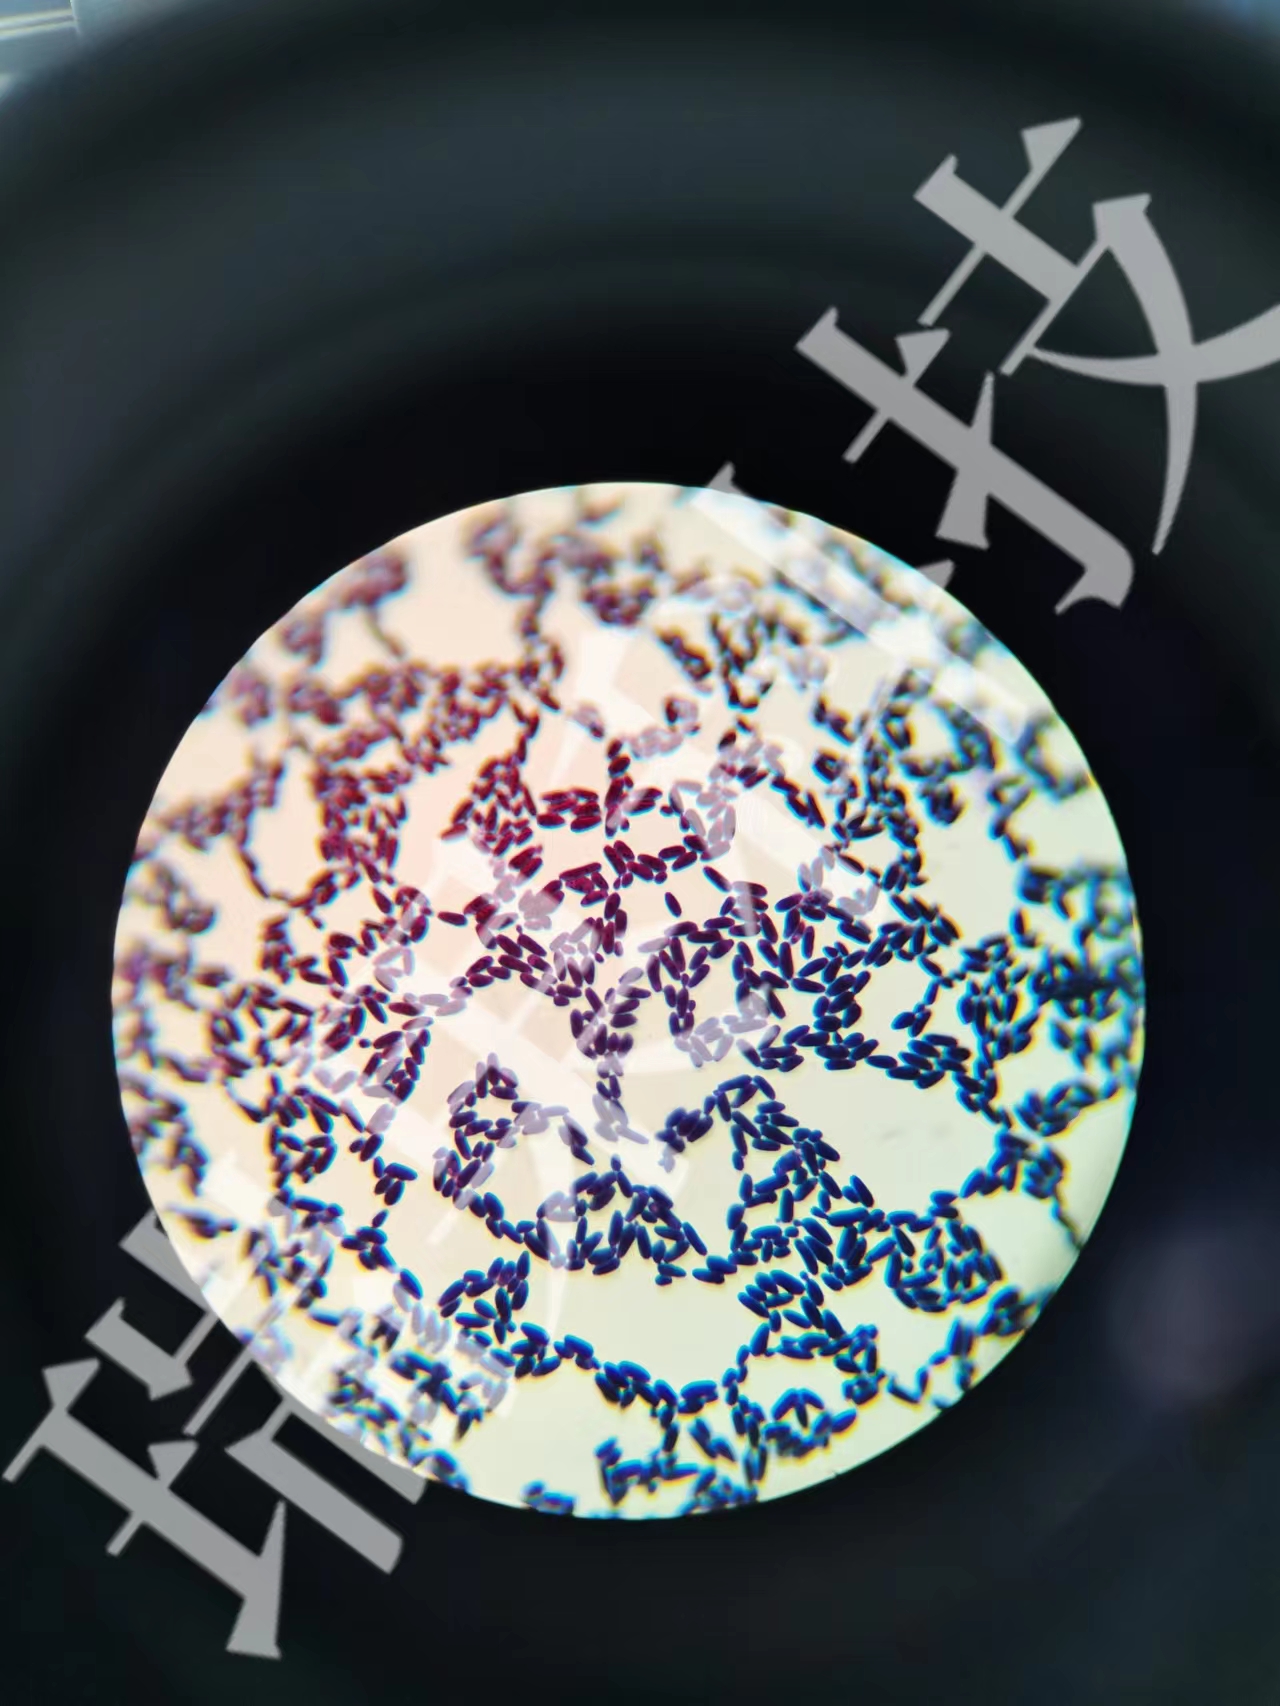

过碘酸-雪夫(Pexiodic acid-schiff,PAS)染色又称糖原染色。胞浆内存在的糖原或多糖类物质(如黏多糖、黏蛋白、糖蛋白、糖酯等)中的乙二醇基(CHOH-CHOH)经过碘酸(Periodic acid)氧化,转变为二醛基(CHO-CHO),与雪夫(Schiff)试剂中的无色品红结合,形成紫红色化合物而沉积于胞浆中糖原类物质所存在的部位。该反应称为过碘酸-雪夫(PAS)阳性反应。